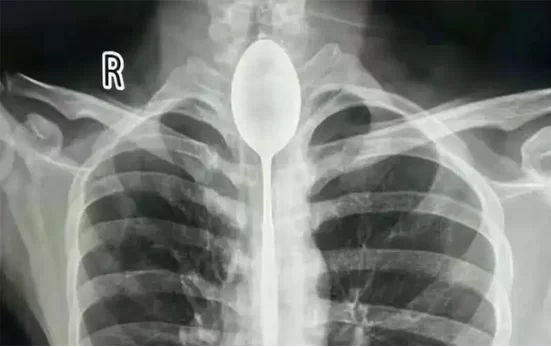

Credit: Xinjiang Meikuang General Hospital

„Domnul Zhang” a ajuns la Spitalul Xinjiang Meikuang din China în octombrie după ce a înghiţit o lingură cu un an mai devreme, lucru care nu i-a cauzat mari probleme, până când au apărut dureri după ce a fost lovit în piept. Trei doctori au înlăturat obiectul de 20 de centimetri într-o procedură care a durat circa două ore. „Nu am întâlnit un asemenea pacient până acum”, a precizat Dr. Xiwu.